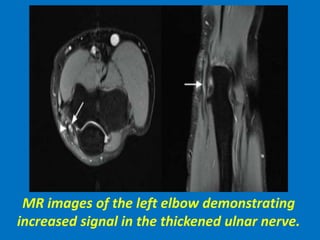

MR images of the left elbow demonstrating

increased signal in the thickened ulnar nerve.

MR images ofthe left elbow demonstrating increased signal in the thickened ulnar nerve.